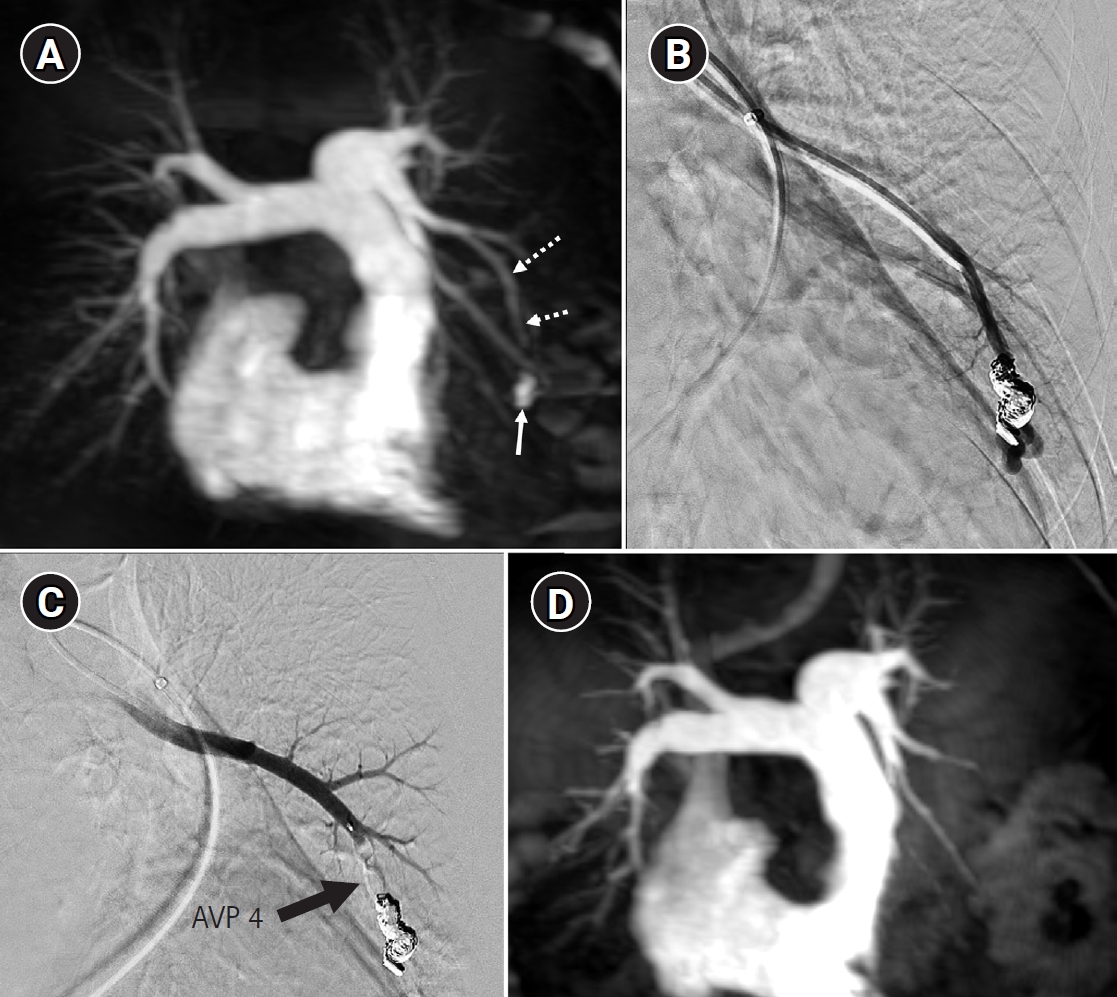

Fig. 6.

Time-resolved magnetic resonance angiography (TR-MRA) and procedural images of a pulmonary arteriovenous malformation showing recanalization. (A) In the TR-MRA performed before the procedure, a venous sac (arrow) is observed concurrently with the feeding artery (dashed arrows). (B) Recanalization was confirmed in the selective angiography. (C) Utilizing additional coils and an 8 mm Amplatzer vascular plug type IV (AVP 4) (arrow), the feeding artery embolization was carried out. (D) On the 6-month follow-up TR-MRA, the feeding artery is no longer visible, and the venous sac is also not observed.

kjir-2026-00010f6.jpg